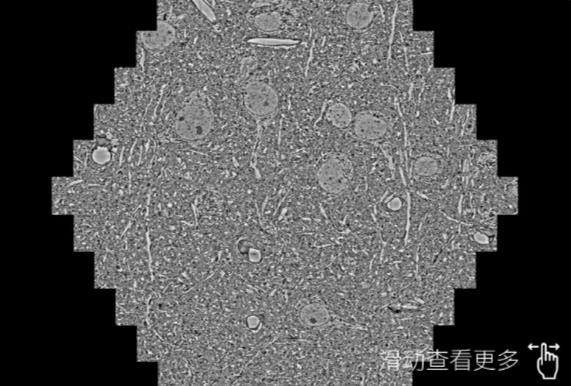

鼠脑切片。左图使用南通蔡司南通扫描电镜MultiSEM706对165μmx143pm面积区域成像,耗时仅需1.5秒。右图为鼠脑切片中30μm区域放大效果。样品由芝加哥大学B.Kasthuri提供。

使用蔡司高速南通扫描电镜MultiSEM对1mm²人脑皮层组织进行高分辨成像,并对其中的各种细胞结构进行三维重构分析。左图展示了2x3mm²组织平面中锥体神经元的三维重构效果。右图显示了局部体积神经元三维重构。图像由哈佛大学chtman实验室提供,渲染图由D. Berger 制作。